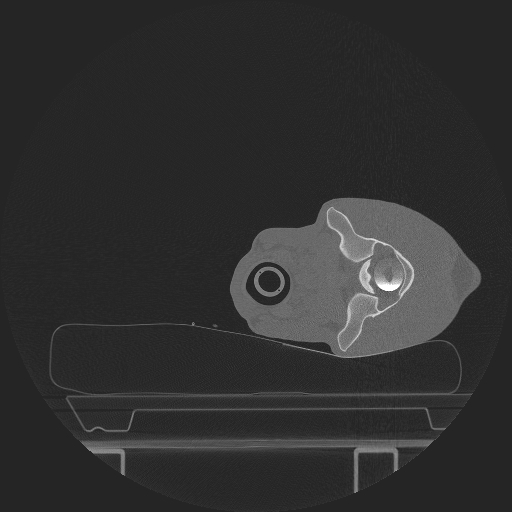

VetTom 8 provides diagnostic quality Computed Tomography (CT) images in a small mobile package. The system is capable of providing at 25 cm field-of-view with high contrast to noise giving you diagnostic confidence for soft-tissue disease and injury.